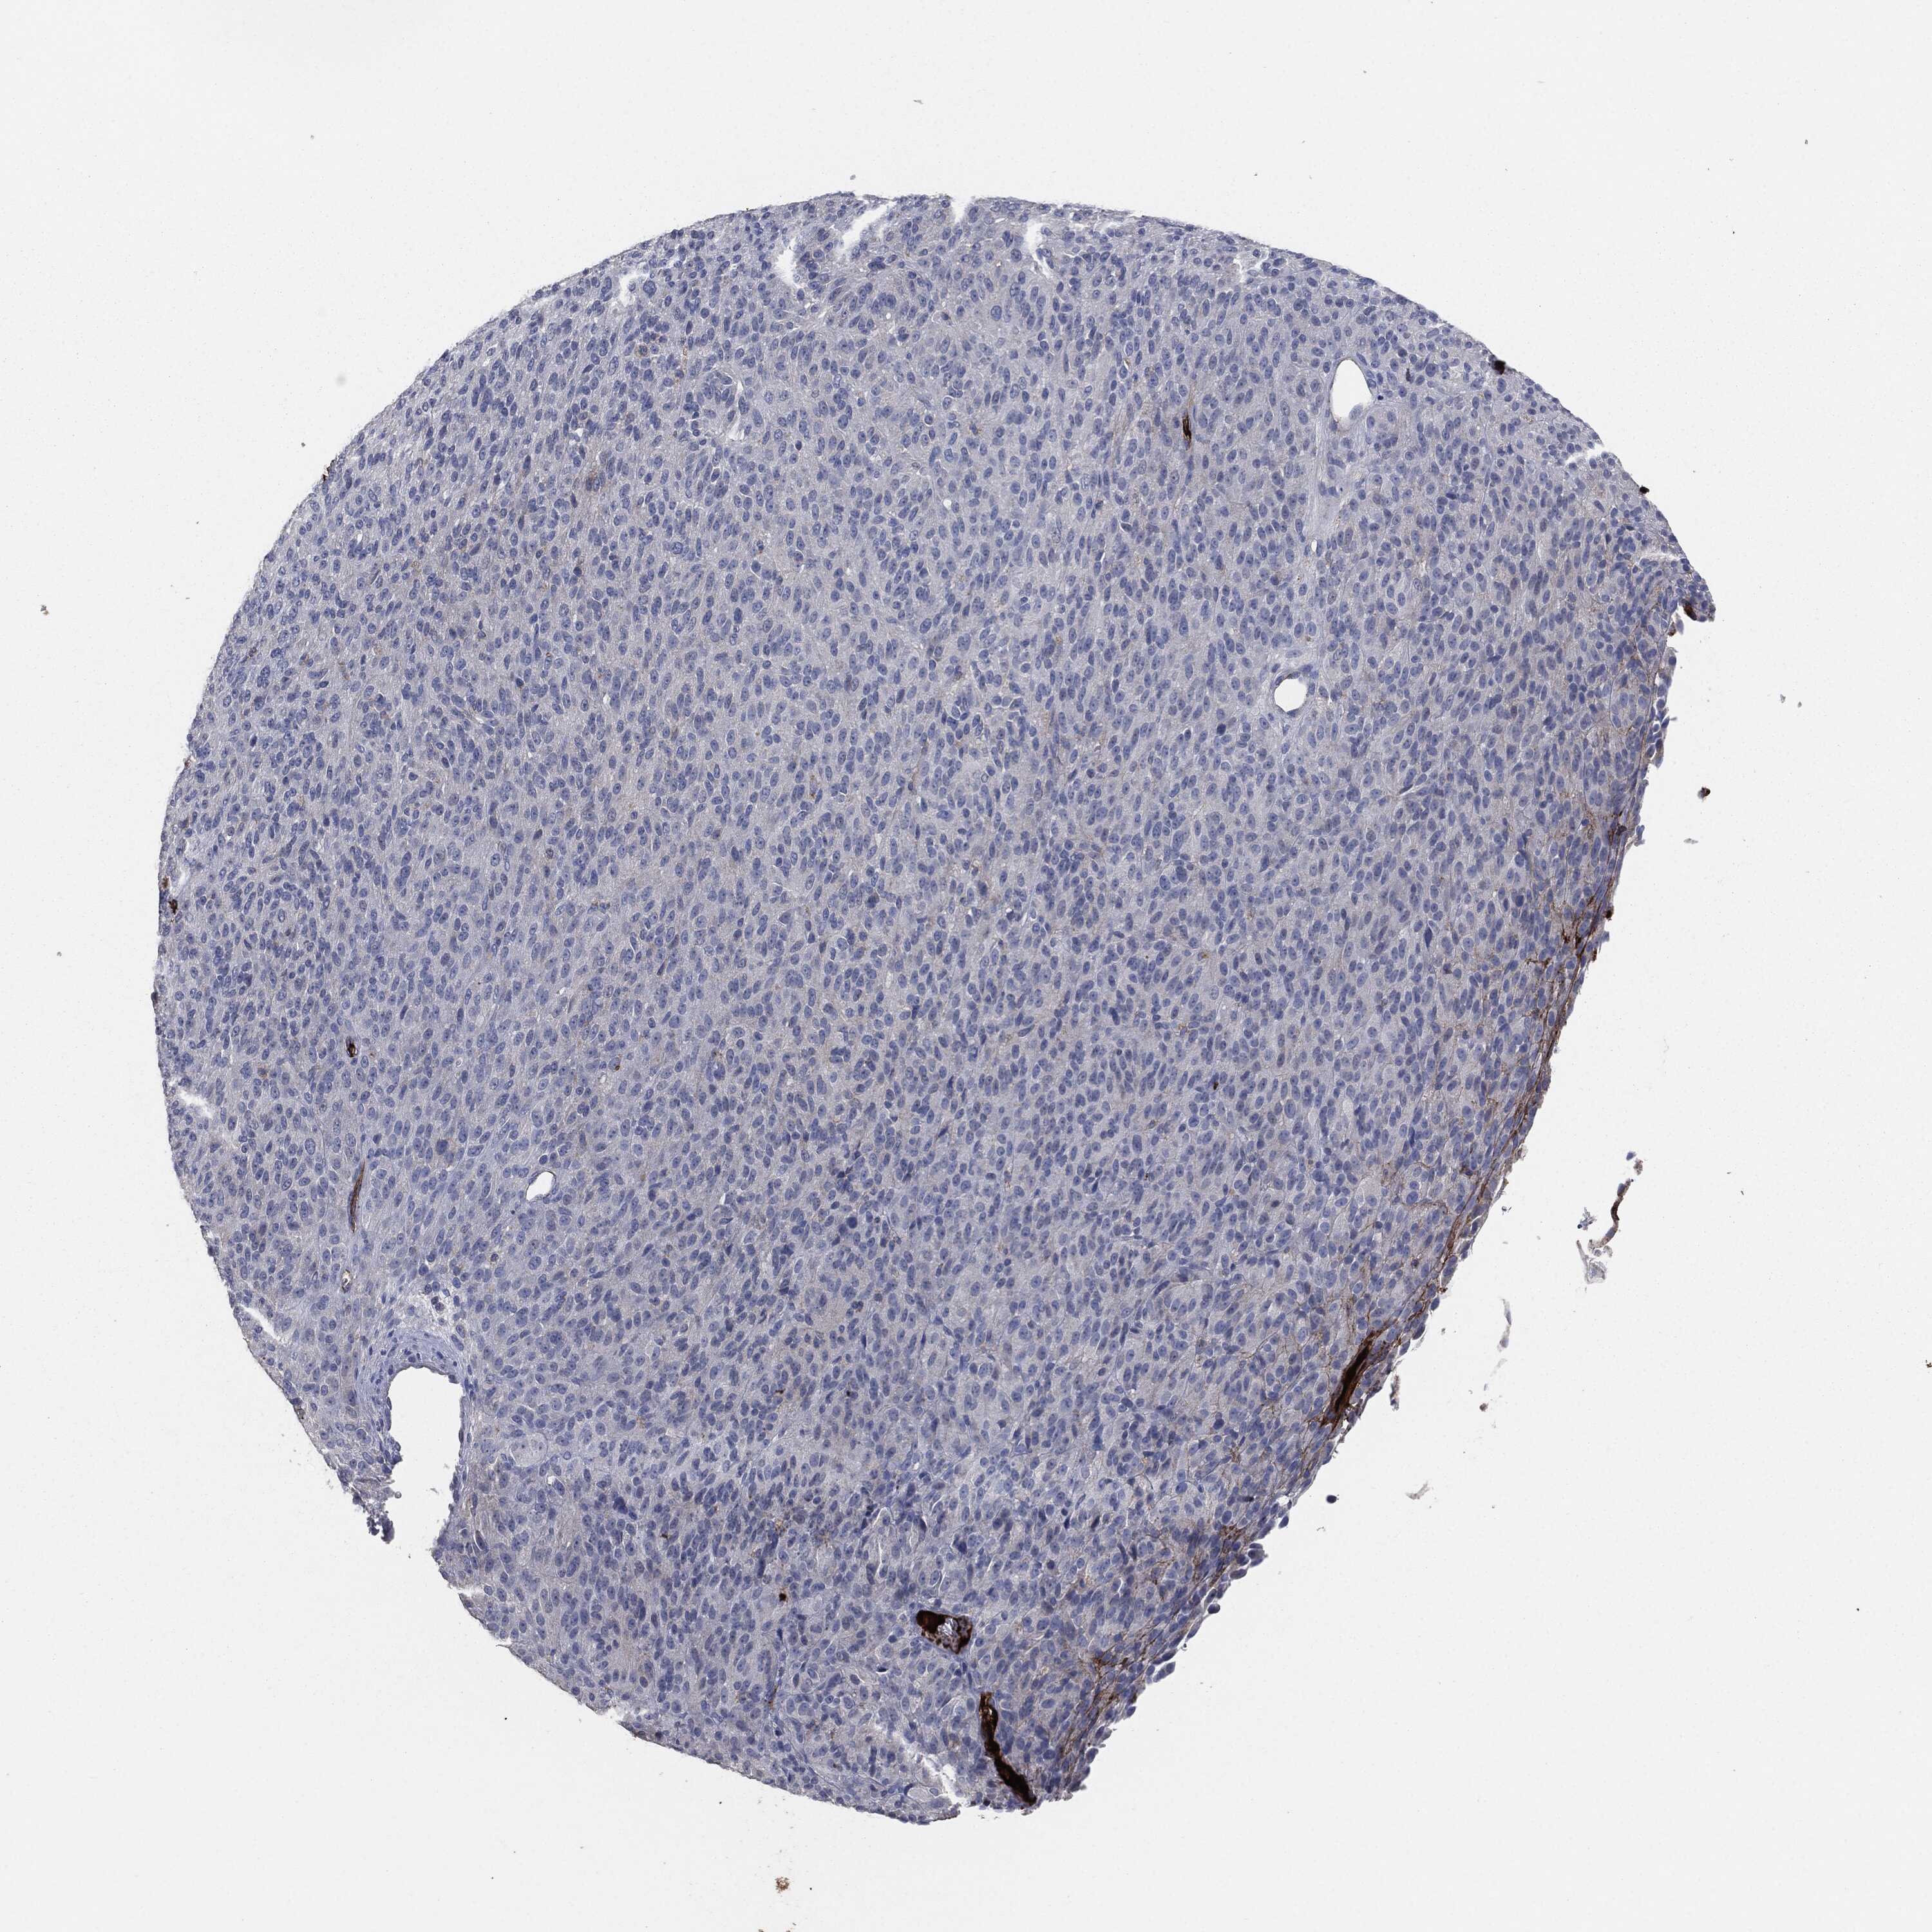

MELANOMA - Protein expressioni

A mouse-over function shows sample information and annotation data. Click on an image to view it in a full screen mode. Samples can be filtered based on level of antibody staining by selecting one or several of the following categories: high, medium, low and not detected. The assay and annotation is described here.

Note that samples used for immunohistochemistry by the Human Protein Atlas do not correspond to samples in the TCGA dataset.

Antibody stainingi

Antibody staining in the annotated cell types in the current human tissue is reported as not detected, low, medium, or high, based on conventional immunohistochemistry profiling in selected tissues. This score is based on the combination of the staining intensity and fraction of stained cells.

Each image is clickable and will lead to virtual microscopy that enables deeper exploration of all samples and also displays staining intensity scores, fraction scores and subcellular localization as well as patient and tissue information for each sample.

HPA049793

CAB016070

CAB080297

CAB080298

CAB080299

Malignant melanoma, NOS

Malignant melanoma, Metastatic site